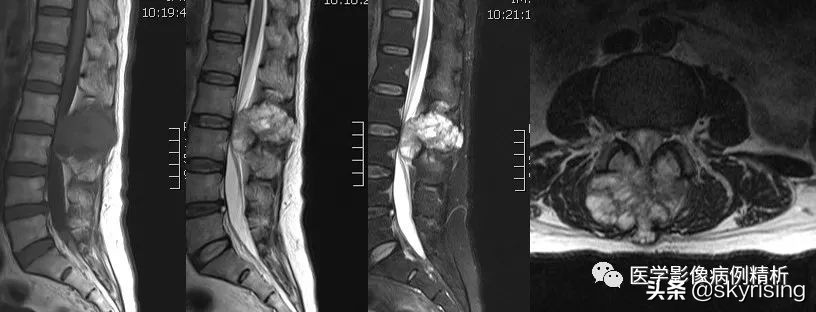

MRI

T1WI矢状位红色箭头所示腰2-3椎体附件区团块状异常信号,T1低信号为主,信号不均,T2WI高信号为主,其内见条形低信号分隔,压脂像明显高信号为主,向前突入椎管,临近蛛网膜下腔扩张呈三角形,相应水平椎管变窄,脊髓受压前移,信号增高,向后直达皮下脂肪层。轴位像椎体棘突、双侧椎弓根骨质破坏,见团块状软组织信号,病灶突入椎管内,相应水平椎管变窄,信号明显不均,其内见多发条形低信号,双侧竖脊肌受压移位。

黄色箭头所示蛛网膜下腔明显扩张, 病灶上下缘呈三角形扩张,脊髓受压信号增高,提示损伤。

绿色箭头可见腰4-5椎间盘髓核 T2 信号减低(注意其他椎间盘),提示间盘变性,纤维环后缘见点状T2及压脂像高信号,T1低信号,提示纤维环撕裂,需警惕椎间盘脱出可能。

红色箭头汇总:腰2-3椎体附件包括棘突、双侧椎弓根骨质破坏,见团块状软组织肿物,T1低信号,T2及压脂像高信号,信号不均,中心见多发条形低信号分隔。病灶向前突入椎管内,蛛网膜下腔扩张,脊髓受压前移、信号增高,向后达皮下脂肪层。轴位像病灶推移双侧竖脊肌,呈分叶状生长。

黄色箭头汇总:病灶向前突入椎管,推移脊髓,蛛网膜下腔扩张。

绿色箭头汇总:腰4椎体纤维环后缘见点状高信号,提示撕裂。